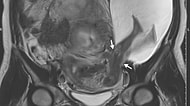

Ayaklarıyla Annesinin Rahim Duvarını Dürtmesi Sonucu Uterusu Yırtan 'Alien' Bebek! 2016 yılı, giderayak son derece ender ve şaşırtı... 28 Aralık 2016